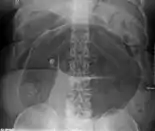

Plain X ray of a cecal volvulus